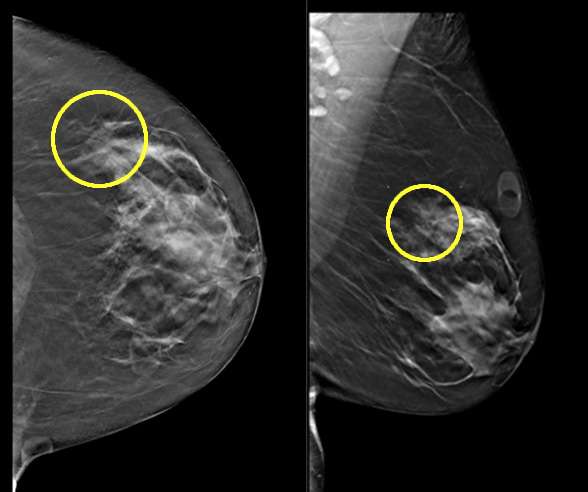

Case: Atypical Lobular Hyperplasia Figure 1

Questionable distortion on screening mammogram. Finding consistent with biopsy proven ALH. There was no sonographic correlate on diagnostic ultrasound (not shown).